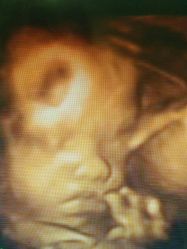

• 杭州贝瑞斯美华妇儿医院·早孕·产检·儿科

• -杭州贝瑞斯美华妇儿医院·早孕·产检·儿科

相册

虾米爱吃重口味 上传于 19-01-10 | 报错